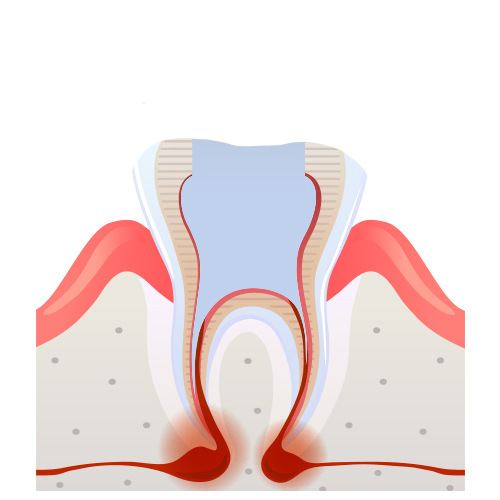

신경치료 과정

07

07

씌우기 전 삭제

08

08

보철을 씌움 신경치료완료